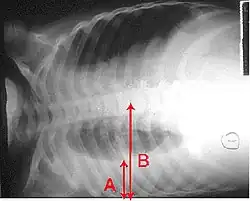

X-ray presentations of pneumonia may be classified as lobar pneumonia, bronchopneumonia, lobular pneumonia, and interstitial pneumonia.[75] Bacterial, community-acquired pneumonia classically show lung consolidation of one lung segmental lobe, which is known as lobar pneumonia.[42] However, findings may vary, and other patterns are common in other types of pneumonia.[42] Aspiration pneumonia may present with bilateral opacities primarily in the bases of the lungs and on the right side.[42] Radiographs of viral pneumonia may appear normal, appear hyper-inflated, have bilateral patchy areas, or present similar to bacterial pneumonia with lobar consolidation.[42] Radiologic findings may not be present in the early stages of the disease, especially in the presence of dehydration, or may be difficult to interpret in the obese or those with a history of lung disease.[24] Complications such as pleural effusion may also be found on chest radiographs. Laterolateral chest radiographs can increase the diagnostic accuracy of lung consolidation and pleural effusion.[41]

Most bacteria enter the lungs via small aspirations of organisms residing in the throat or nose.[24] Half of normal people have these small aspirations during sleep.[29] While the throat always contains bacteria, potentially infectious ones reside there only at certain times and under certain conditions.[29] A minority of types of bacteria such as Mycobacterium tuberculosis and Legionella pneumophila reach the lungs via contaminated airborne droplets.[24] Bacteria can also spread via the blood.[25] Once in the lungs, bacteria may invade the spaces between cells and between alveoli, where the macrophages and neutrophils (defensive white blood cells) attempt to inactivate the bacteria.[57] The neutrophils also release cytokines, causing a general activation of the immune system.[58] This leads to the fever, chills, and fatigue common in bacterial pneumonia.[58] The neutrophils, bacteria, and fluid from surrounding blood vessels fill the alveoli, resulting in the consolidation seen on chest X-ray.[59]